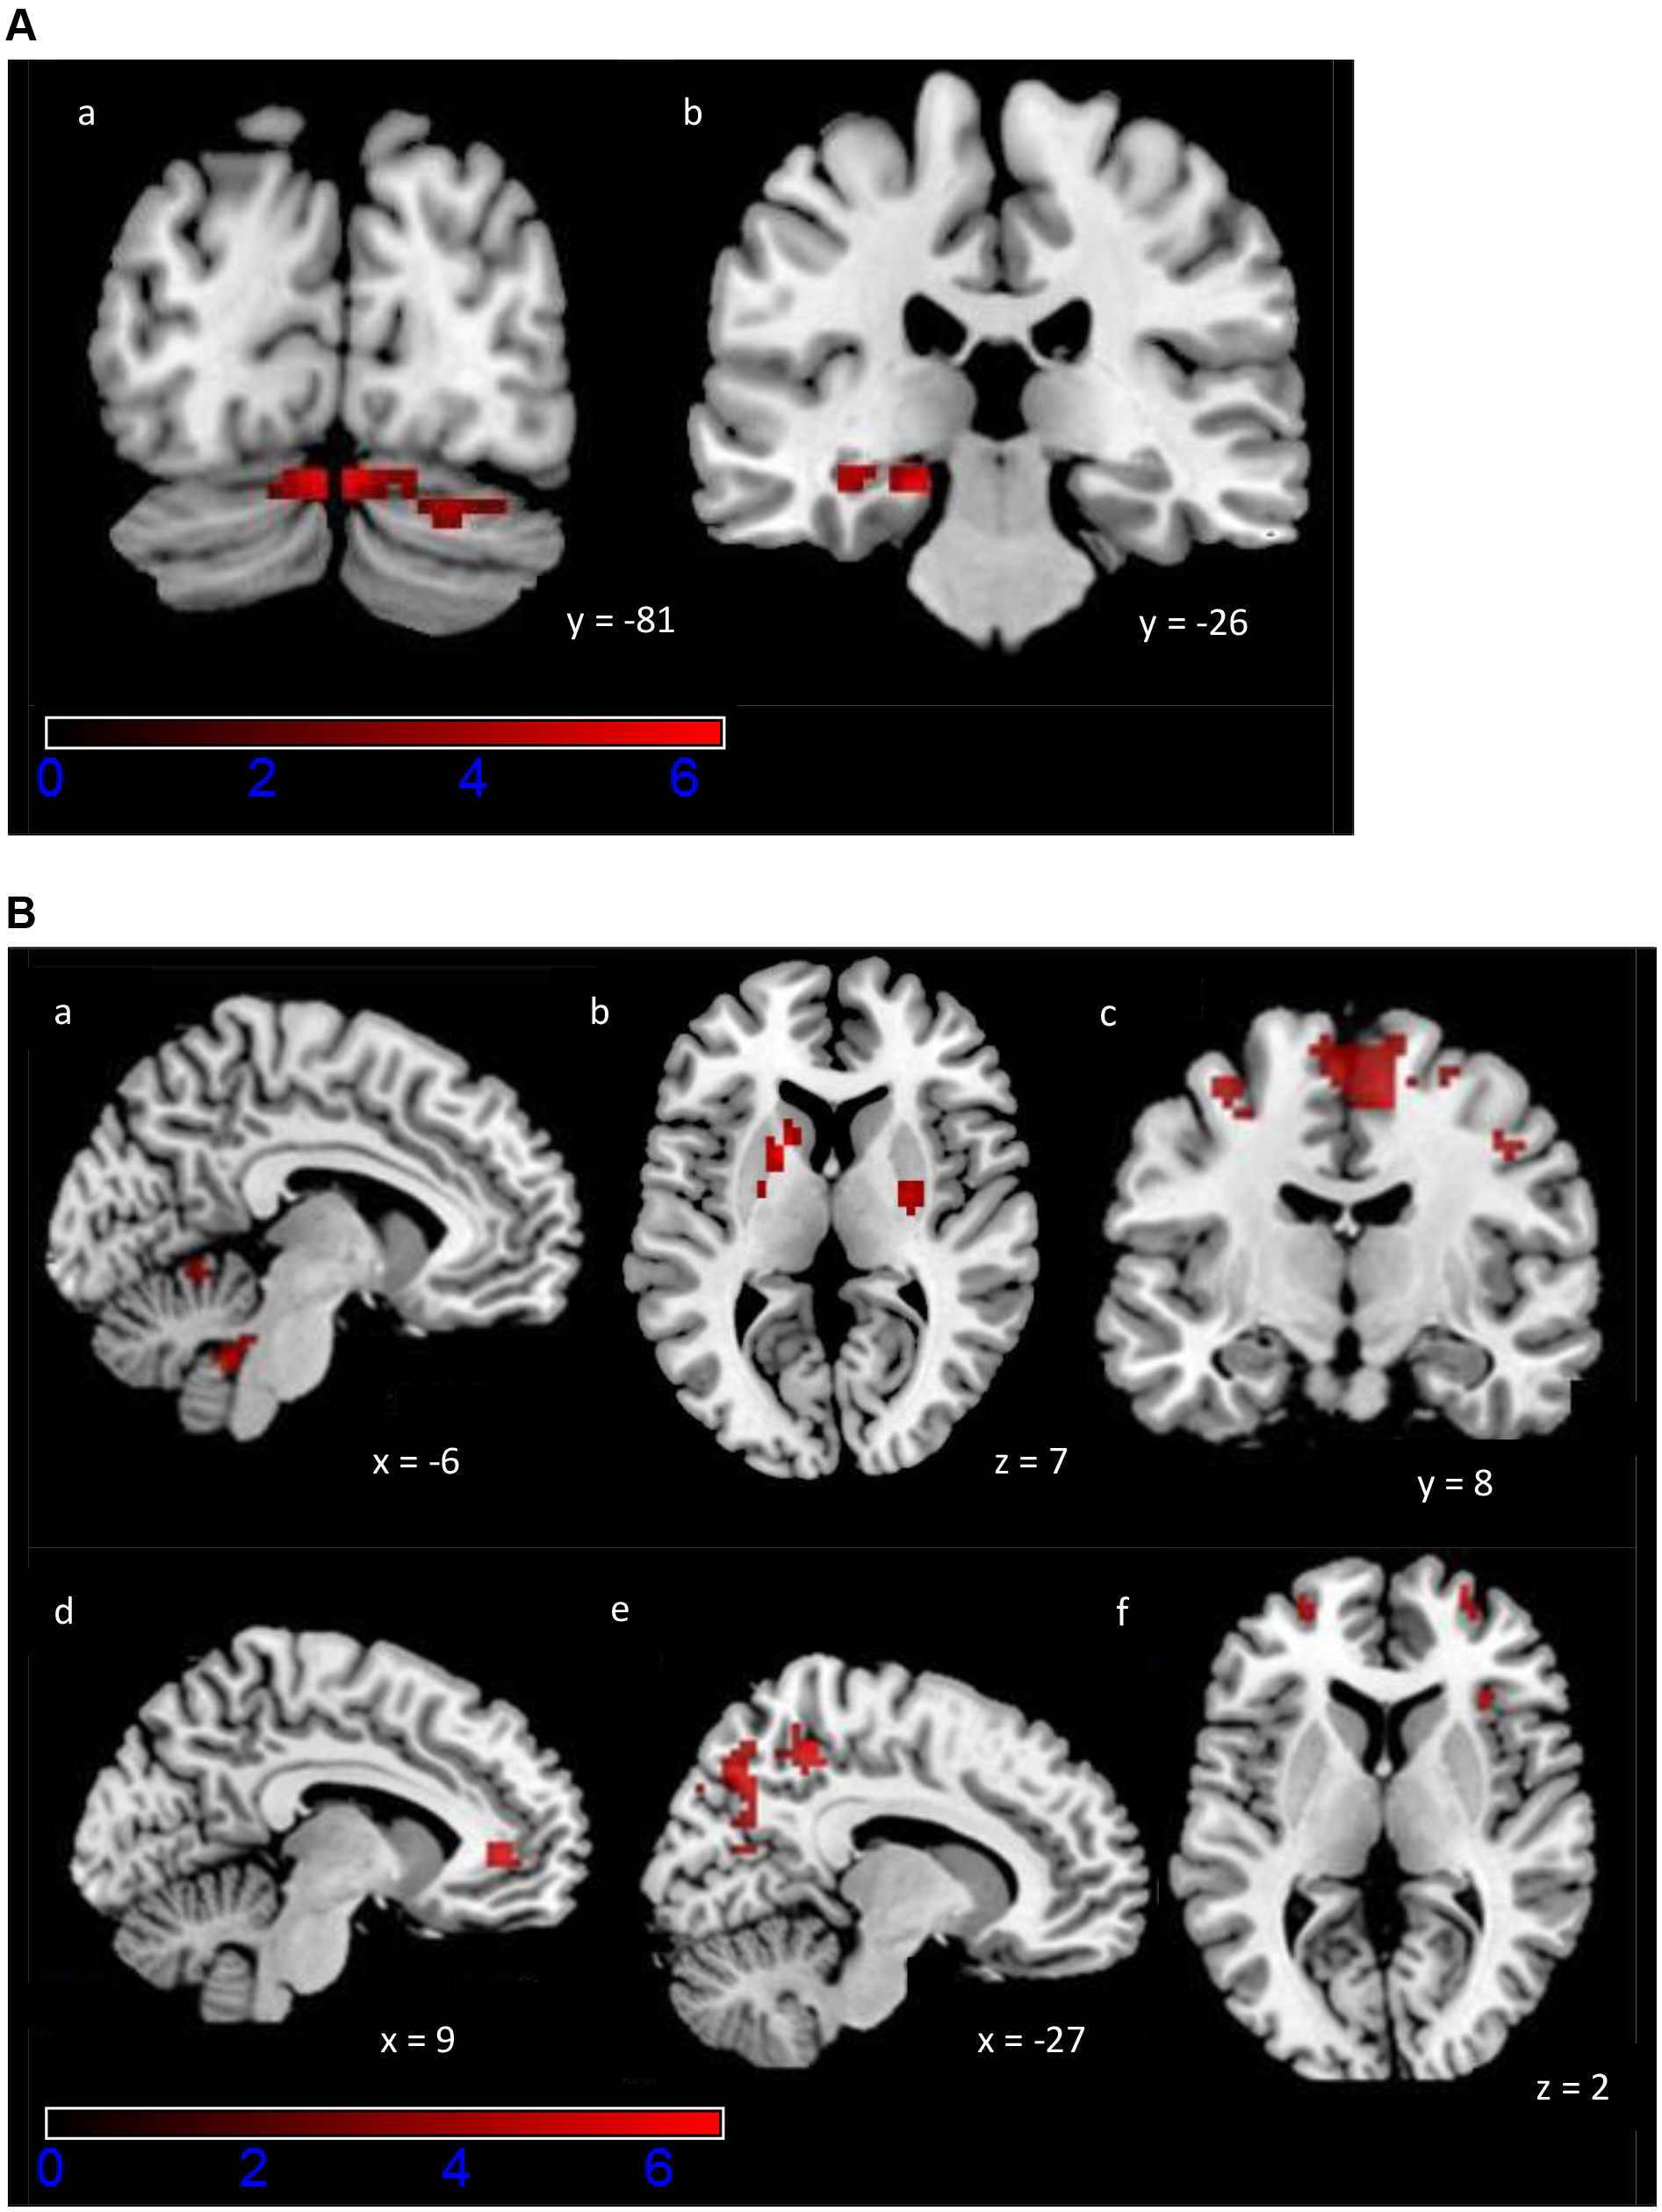

Fig. 3. Activation maps of the exploratory ROI analysis for the PCM task. Colour scale indicates z-scores, ranging from 0 to 6. (A) Increased activity during Early Learning (a) bilaterally in cerebellum, (b) left parahippocampal gyrus and hippocampus. A statistical significance of p

We examined the differences in testing phase more closely using the contrasts Early

| Left cerebellum (Crus 2) | –3 | –85 | –22 | 6.77 | 159 | 0.014 | |

| Right cerebellum (Crus 1) | 6 | –85 | –19 | 6.24 | |||

| Right lingual gyrus | 21 | –94 | –7 | 5.25 | |||

| Right cerebellum (Crus 2) | 6 | –85 | –25 | 4.15 | |||